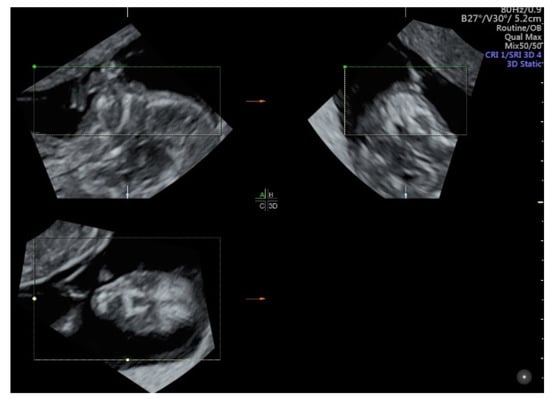

2.2. Face and Neck

- Mak, A.S.L.; Leung, K.Y. Prenatal ultrasonography of craniofacial abnormalities. Ultrasonography 2019, 38, 13–24. [Google Scholar] [CrossRef] [Green Version]